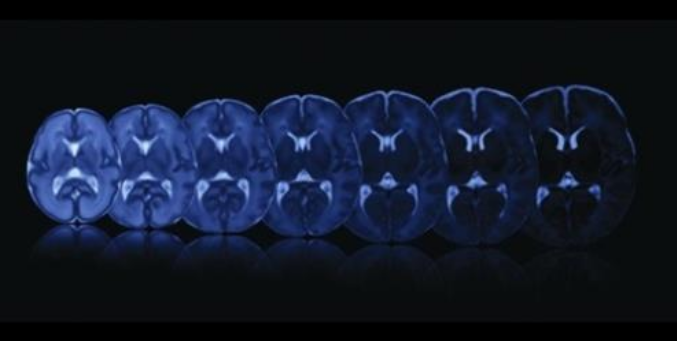

• CIBERBBN

Nuevas técnicas para el estudio de la maduración del cerebro durante el embarazo

04/10/2021